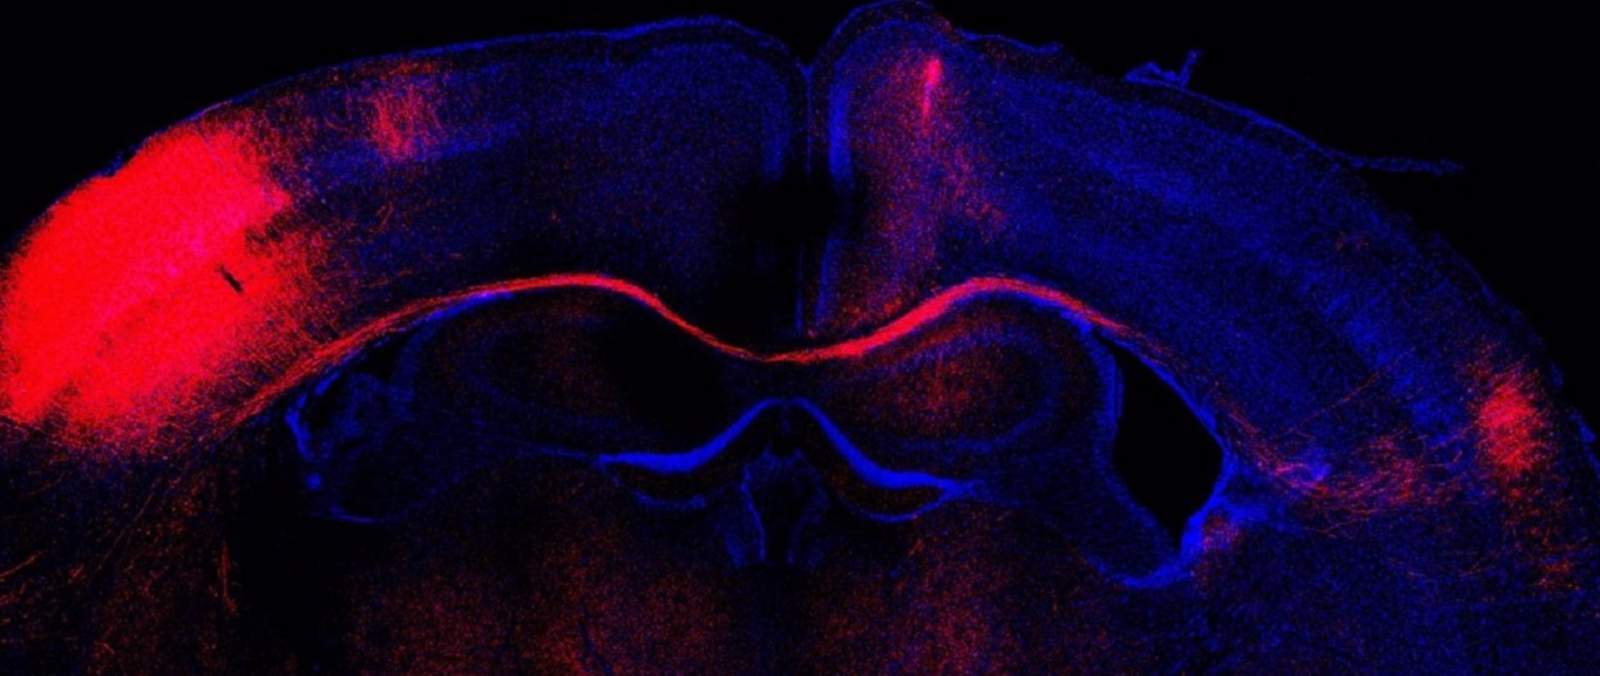

Imagen de microscopía de un corte cerebral con las conexiones formadas por neuronas (rojo). - LORENA BRAGG-GONZALO, CNB-CSIC

Un hallazgo del Consejo Superior de Investigaciones Científicas (CSIC) ha identificado cómo las neuronas inhibitorias determinan la estabilización o eliminación de las estructuras de comunicación excitatoria al filtrar las señales que reciben las neuronas excitatorias durante su maduración y, por tanto, determinan la estructura final del cerebro adulto.

"Nuestros datos demuestran que manipulaciones tempranas en las neuronas inhibitorias inducen cambios estructurales en sus vecinas excitatorias. Estas alteraciones ocasionan, en consecuencia, cambios persistentes en su manera de conectarse que afectan a un correcto procesamiento y computación de la información sensorial. La inhibición temprana en el cerebro en formación, por tanto, determina la estructura del cerebro adulto", ha señalado una de las primeras autoras del trabajo, Lorena Bragg-Gonzalo.

Para Alfonso Aguilera, también primer autor del artículo junto a Bragg-Gonzalo, e investigador del CNB-CSIC, aclara que "estos datos sitúan a las neuronas inhibitorias como cimientos fundamentales para el ensamblaje y formación de módulos de comunicación entre áreas del cerebro en las primeras etapas del desarrollo. Al mismo tiempo, alteraciones en estas neuronas inhibitorias, antes asociadas a enfermedades del neurodesarrollo, pero desconociendo el cómo, son capaces de inducir defectos permanentes en el circuito neuronal adulto".